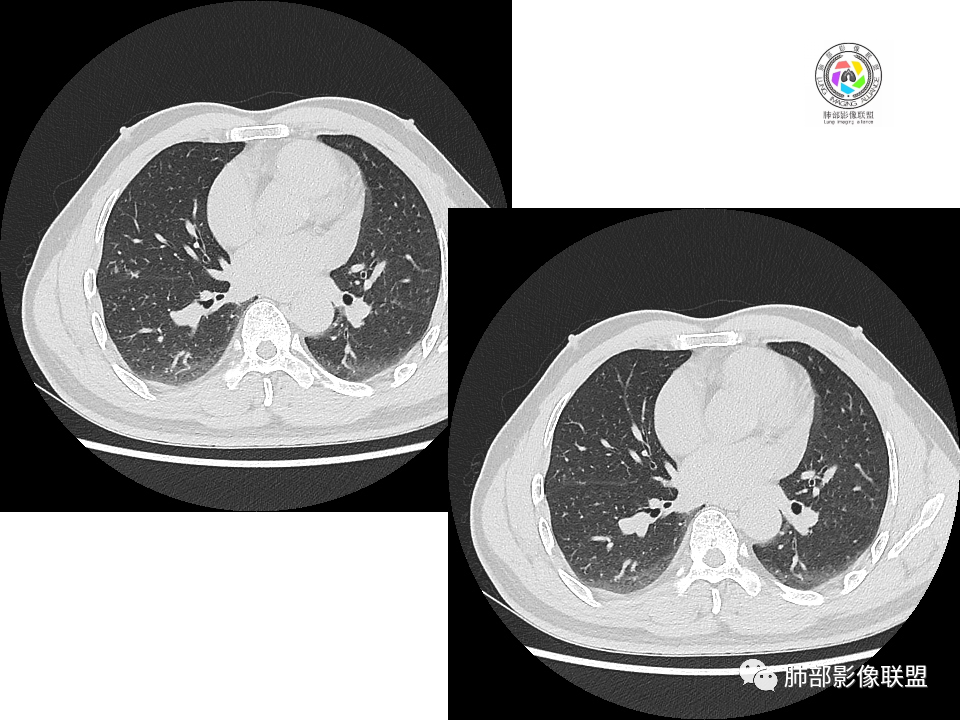

右肺中叶病灶

GGO,与支气管关系密切

这个形态、与支气管关系,与前两个不一致,所以考虑独立炎性病变。

2.右肺下叶背段胸膜下块影,边界清楚光整,上下极见磨玻璃晕,未见明显分叶毛刺和棘状突起,未见胸膜凹陷或胸壁侵入。密度均匀,轻度不均匀强化。未见支气管进入。

3.右肺中叶外侧段胸膜下散在小片影,磨玻璃密度为主,边界不清,支气管相关。符合炎性特征!

4.右肺下叶基底段支气管血管束旁小结节影,边界清楚,强化不明显。注意,这结节在“遥远的”基底段。

显然本例焦点在于背段那个边缘光整的块影!

5.慢性感染灶。缺乏临床表现,强化不显著会想到继发性肺结核,背段病灶过于光整均匀,周边过于干净使人狐疑,且“成掎角之势”的中叶病灶结核灶特点也着实不多。

有老师分析,多发病灶有磨玻璃晕,可以符合隐球菌感染,确实如此。但背段边缘如此锐利的块影还是更容易让人联想到新生物。

关于结节型隐球菌

1、普通人隐球菌感染的时相:初期的隐球菌感染周围有晕,晕从多变少,或包裹,或吸收,结节实性区可迅速变大。后期(慢性期)的隐球菌周围无明显晕征,边界较清楚。

3、卫星灶与“蘑菇兄弟”:诊断隐球菌时,建议找卫星灶,卫星灶可以在遥远的地方。可以是遥远地方的微小结节——“小蘑菇兄弟”。有些远处的卫星灶,通常是不规则饱满实性的,晕征不明显。隐球菌的卫星灶非常“隐”,但发现率高达60%多,诊断价值高。

5、周围毛刺纤维、边缘形态等:坏死包裹会使得结节变圆;结节多缺乏明显的分叶征,缺乏局部突出生长能力;如果出现分叶,是由多处肉芽肿中心形成。没有坏死的局限化,结节只是凑合在一起,常呈方形征;毛刺进入晕区(概念源自南边老师),毛刺较短、较软;周围的晕吸收后,会留下不规则边,外面常残留丝状条索;收缩力较弱,临近胸膜对胸膜牵拉不明显。